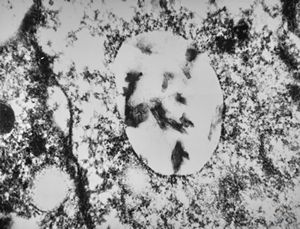

F,50y. | progressive multifocal leukoencephalopathy- viral particles in a glial cell

F,50y. | progressive multifocal leukoencephalopathy- viral particles in a glial cell

F,50y. | progressive multifocal leukoencephalopathy- viral particles in a glial cell